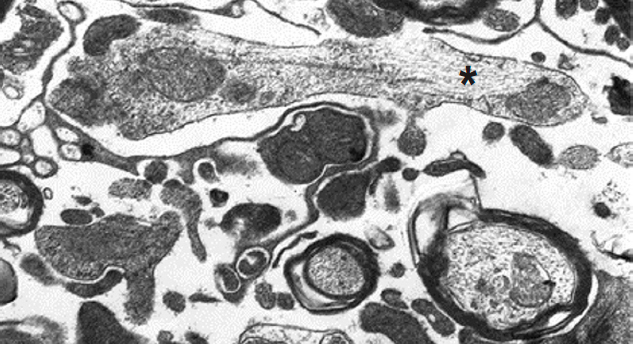

Notably, axonal growth cones were observed in the spinal cords of the treated rats at this stage. Some were pale and contained vesicles, mitochondria, RER, microtubules, and neurofilaments (Fig. 6), whereas others were hyperchromic and boot-like in shape (Fig. 7).

Fig. 6. Growth flask from an axon with light axial cylinder (*), ×5,000.

Рис. 6. Колба роста из аксона со светлым осевым цилиндром (*), ×5 000.

Fig. 7. Growth flask from a hyperchromic axon in the form of a boot (1). 2 — process of normal axial cylinder, ×26,000.

Рис. 7. Колба роста из гиперхромного аксона в виде сапога (1). 2 — отросток oбычного вида, ×26 000.